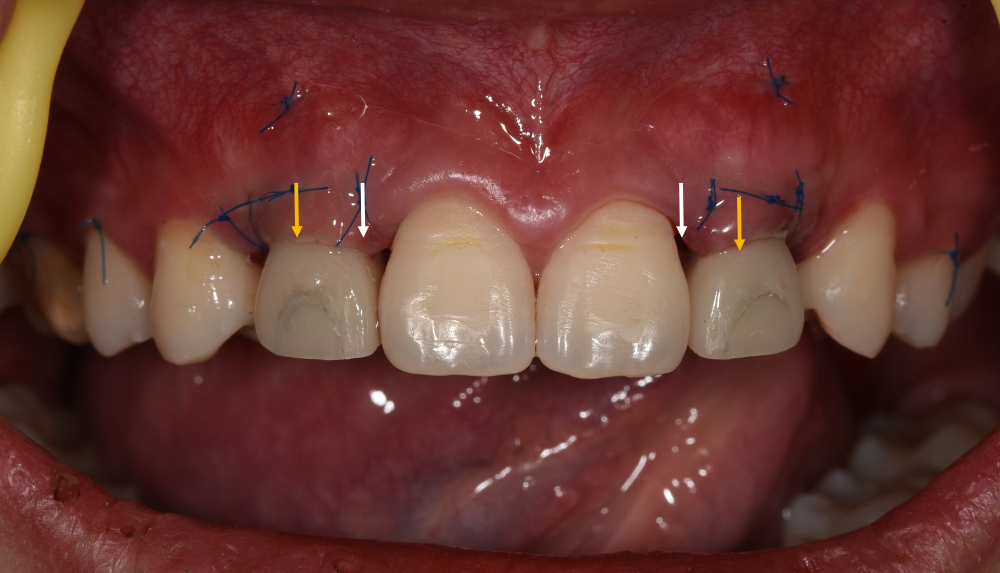

就位临时基台并将预成的树脂牙冠在口内Pick-Up

白色箭头示黑三角,原因分析:

1.因不是即刻种植,龈乳头处的软组织已是平坦的,缝合后龈乳头的形态欠佳

2.龈缘位置(黄色尖头示)较理想龈缘偏冠方,临时修复体颈部关键区凸起造成张力

改进:先将临时修复体关键区设计在冠根方,先确保龈乳头愈合良好,后期再塑形

戴入临时修复体正面观